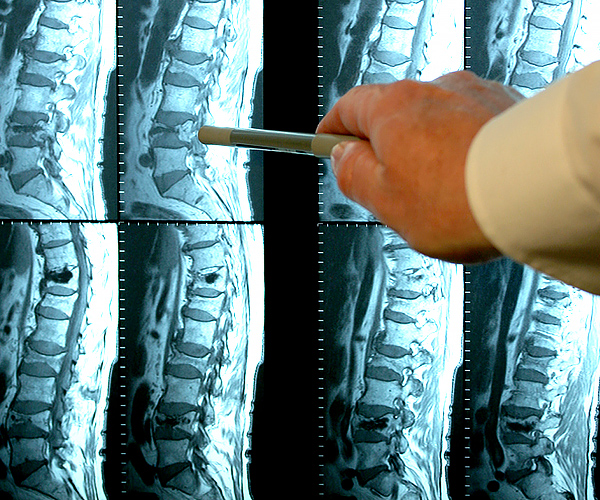

Sarah Sibanda : Je n'ai pas trop envie d'en parler en public, ma motivation est purement personnelle. Il y a quelques années, ma mère est décédée d'une septicémie, elle souffrait de douleurs articulaires depuis des années. Pendant les examens, les tissus articulaires avaient l'air et les médecins n'étaient pas inquiets, mais parfois ma mère se plaignait de douleurs articulaires. Au fil du temps, la douleur a augmenté et elle était hospitalisée. Nous avons continué le traitement, mais à cause de négligence du médecin et des mauvais médicaments, une infection s'est développée dans son sang. Elle est décédée rapidement de septicémie. D'ailleurs, je dois dire que ma grand-mère est aussi morte à cause de ça. Après avoir perdu ma mère, j'ai commencé ma recherche, et quand j'ai vu les résultats, c'était un véritable choque. Parce que j'ai réalisé que les prescriptions écrites par les médecins et les médicaments vendus en pharmacie sont en fait inutiles, voire nuisibles pour le corps. Imaginez que ma mère prenait ces médicaments tous les jours !

Femme de 54 ans. Son articulation est entièrement restaurée. La durée du traitement : 14 jours :